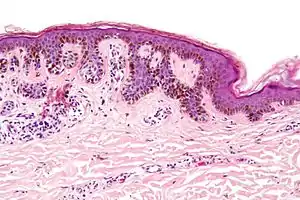

Micrograph of a dysplastic nevus showing the characteristic rete ridge bridging, shouldering, and lamellar fibrosis. H&E stain.